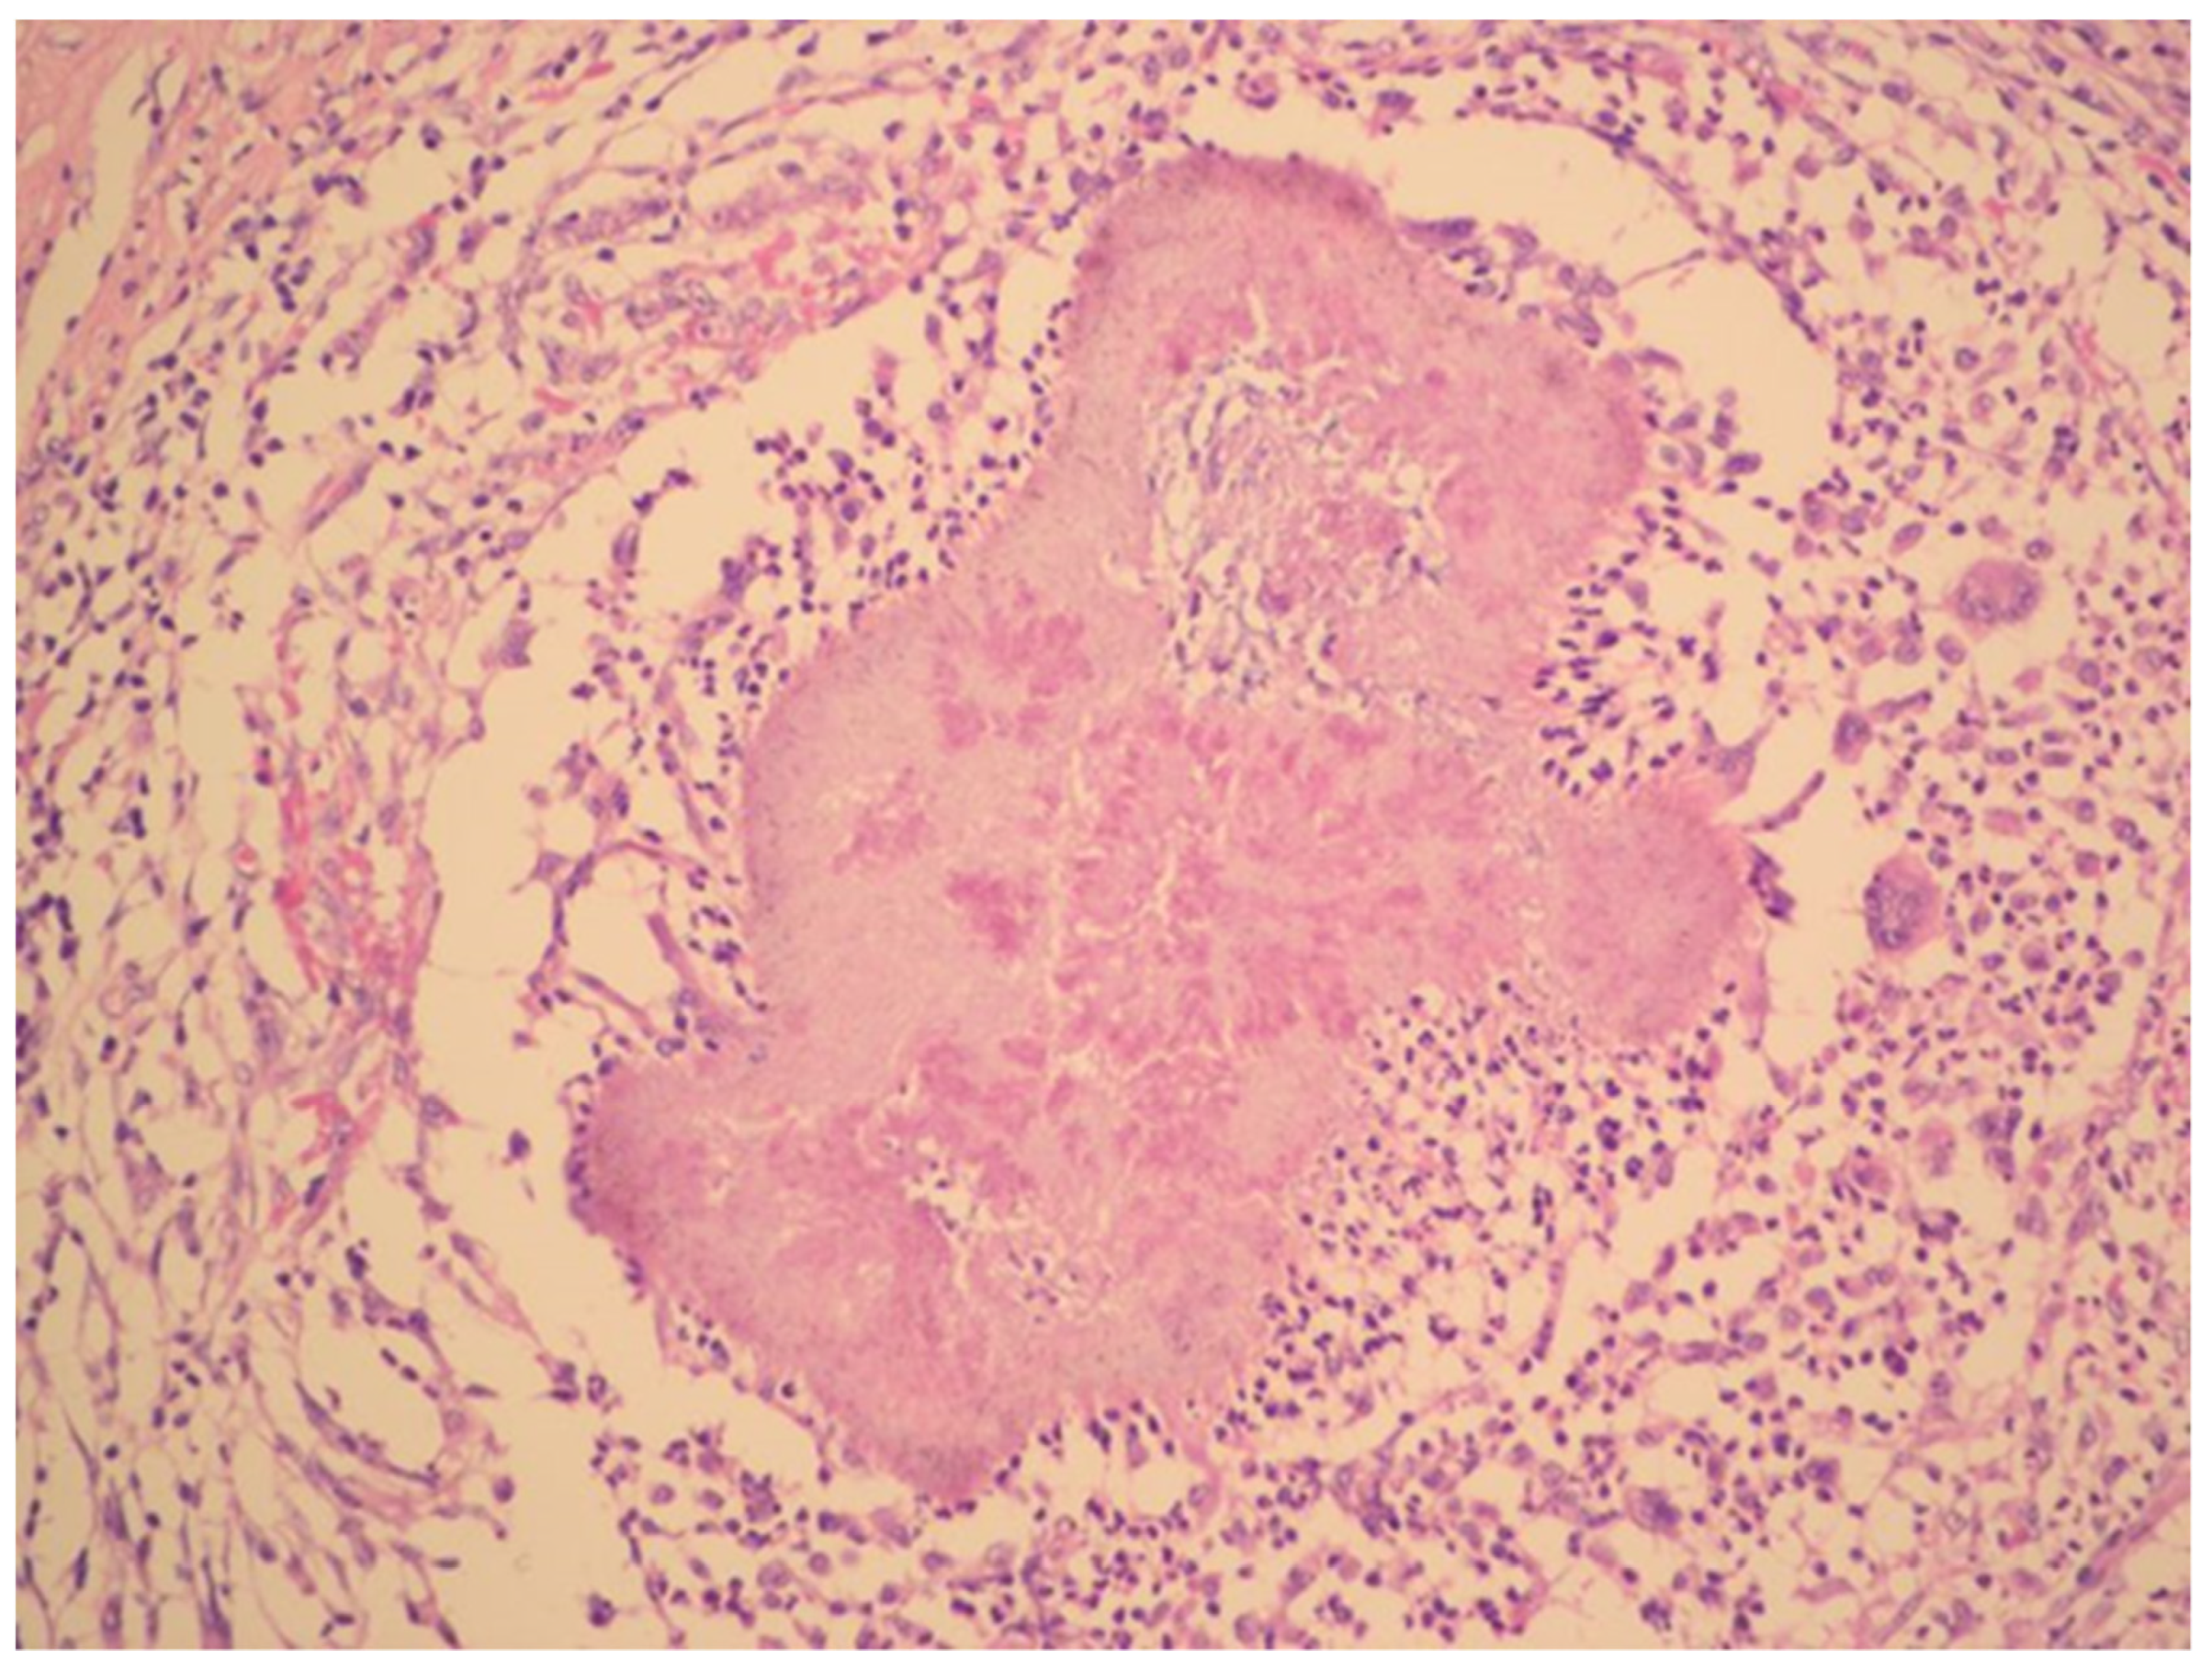

The diagnosis of metastatic ovarian cancer was assumed. Histology of a CT-guided fine-needle liver biopsy sample revealed fibroproliferative inflammation and chronic abscess with actinomycotic granules.

The radical surgery was postponed for two months until the patient´s nutritional status improved. Hysterectomy, bilateral salpingo-oophorectomy, appendectomy and adhesiolysis was performed. On the cut, the mass on the right ovary, with dimensions of 50 × 50 × 30 mm, showed yellowish tissue with necrosis. Histopathology showed that the mass consisted of confluent granulomas with purulent exudate containing fibrillar structures corresponding to actinomycotic granules despite two months of targeted antibiotic treatment (Figure 3).

Figure 3. Histopathology shows granuloma with purulent exudate and actinomycotic granules. Haematoxylin–eosin stain. (With kind permission of Dr. Kamila Benková, Department of Pathology, Hospital Na Bulovce.).